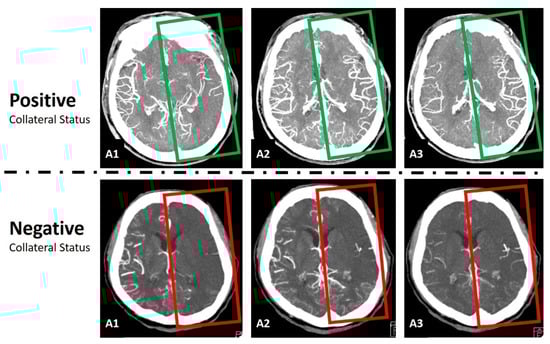

2.3. Data Preprocessing and Normalization

2.4. Convolutional Neural Network